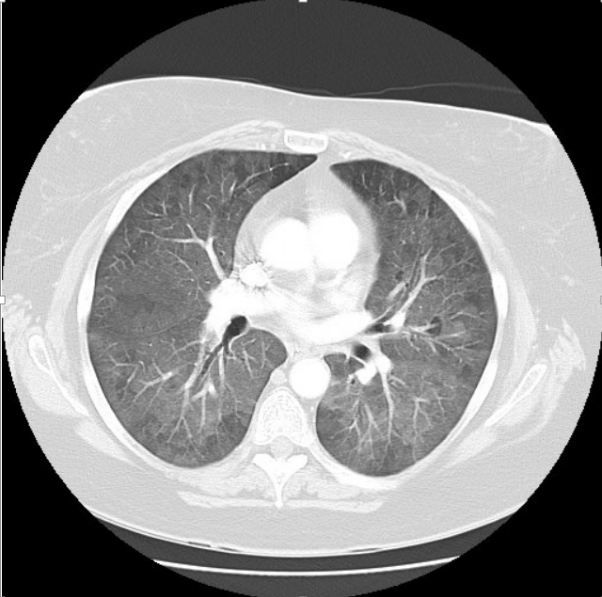

DALLAS--Which patients are candidates for antifibrotic therapy? Is extracorporeal membrane oxygenation appropriate for all ILD patients? The topics were hotly debated on Monday at the American Thoracic Society meeting.